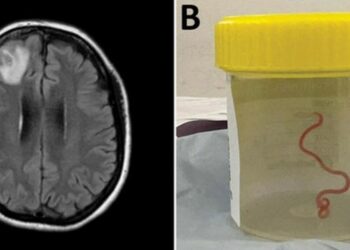

أستراليا: اكتشاف دودة حية في دماغ امرأة لأول مرة في العالم

أعلن العلماء أنه تم العثور على دودة طولها 8 سم حية في دماغ امرأة أسترالية، إذ تم إدخال المريضة إلى...